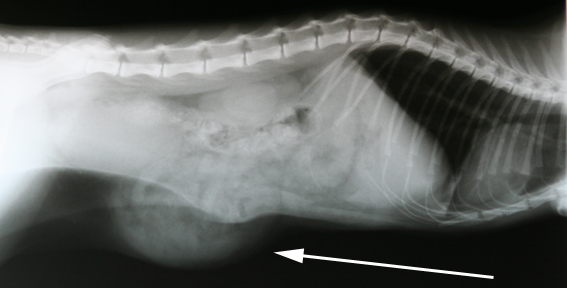

Otje uit Wadenoijen kwam bij ons op afspraak voor de sterilisatie. De eigenaar vertelde dat Otje vlak voor de geplande opname weg was geweest en strompelend was thuisgekomen. Bij het nakijken, door de dierenarts, viel onder andere op dat de nagels afgesleten waren en dat er een vreemde bult onder haar buik zat. Mogelijk was er hier sprake van een aangereden kat. In deze bult leken ook organen te zitten. Vanwege deze gevonden afwijkingen hebben we een röntgenfoto gemaakt. Hierop bleek het middenrif gelukkig intact, maar bleek er inderdaad een breuk, mogelijk wel 2, van de buikwand aanwezig te zijn. Dat wil zeggen dat de buikspieren kapot zijn en als gevolg daarvan buikorganen direct onder de buikhuid komen te liggen.